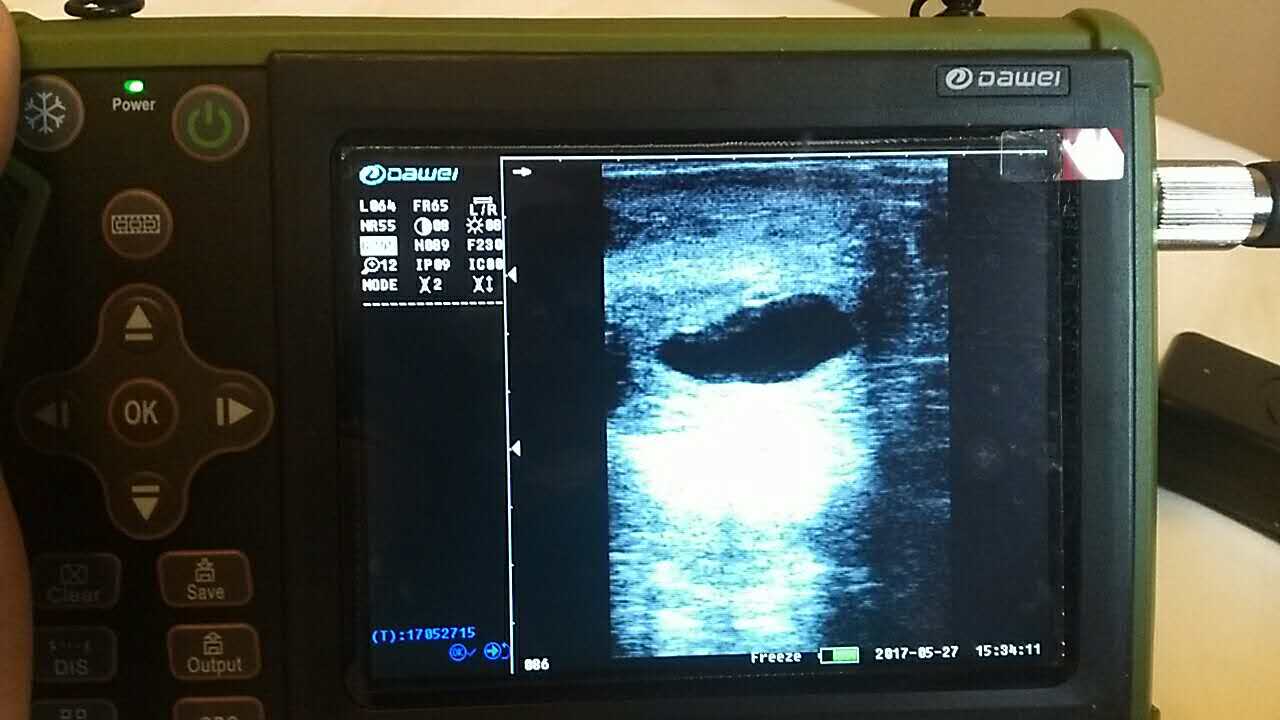

| 羊場(chǎng)母羊照B超辨受孕促增產(chǎn) |

養(yǎng)殖基地140只生產(chǎn)母羊集體接受了B超檢查,利用現(xiàn)代化技術(shù)方法,解決生產(chǎn)母羊繁育難題促進(jìn)畜牧業(yè)生產(chǎn)結(jié)構(gòu)的調(diào)整。 在檢查中,技術(shù)人員拿著B超儀器,給生產(chǎn)母羊做免費(fèi)受孕普查。用B超檢測(cè)母羊受孕情況,用這種方法給母羊做檢測(cè)可以準(zhǔn)確掌握母羊是否受孕、母羊生產(chǎn)周期。通過(guò)B超早期孕檢和生殖系統(tǒng)疾病診斷,可以清晰的觀(guān)測(cè)到生產(chǎn)的宮腔和胎兒的生產(chǎn)發(fā)育情況。除了幫助基地對(duì)問(wèn)題羊做出正確診斷,提出合理的治療方案,淘汰無(wú)治療價(jià)值的長(zhǎng)期空懷羊,還能提高受孕率,降低飼養(yǎng)成本,有效規(guī)避了假妊娠造成的經(jīng)濟(jì)損失。

檢測(cè)懷孕 估測(cè)胎仔數(shù) 疾病診斷 胎兒活力鑒定 胎心搏動(dòng) 適用對(duì)象:適用于羊、豬、狗等動(dòng)物受孕診斷(集成6種常見(jiàn)動(dòng)物孕周測(cè)量數(shù)據(jù)包) 適用范圍:規(guī)模化豬場(chǎng),人工授精站,飼料/獸藥經(jīng)銷(xiāo)商及企業(yè),科研教學(xué)單位 |